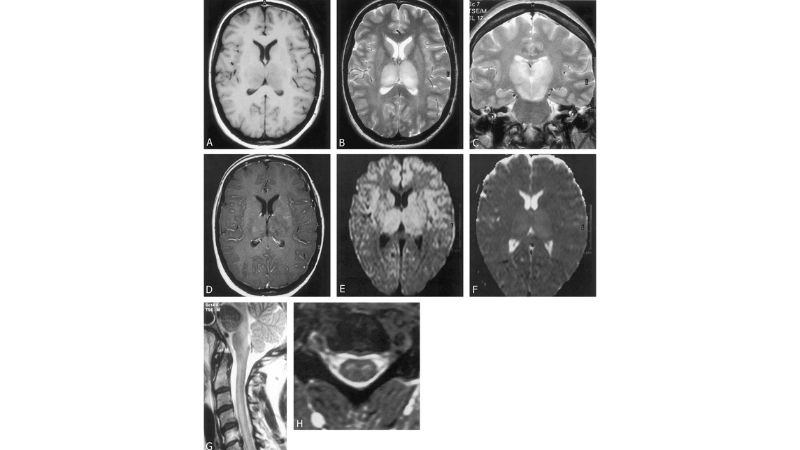

Image description of Murray Valley Encephalitis

Murray Valley Encephalitis is a rare but serious viral infection transmitted by mosquitoes, primarily affecting the brain and nervous system, with potential life-threatening complications.